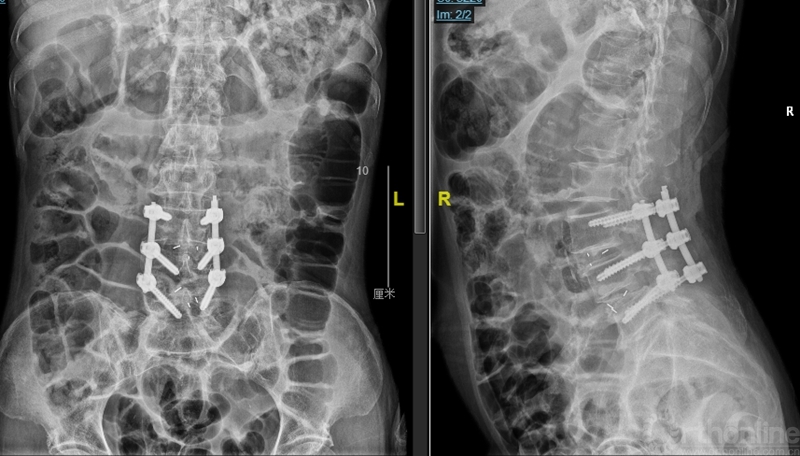

图4:第一次术后X ray

观察24小时后无明显改善,再次行开放腰椎全椎板扩大减压术,近端矢状面扩大减压延伸过腰椎矢状面顶椎(图8),左侧腰4、5及骶1神经根管扩大减压,直至肉眼辨别无明显交界区卡压和神经根紧张(图9)。

图8:第二次减压近端延伸至腰2椎体后方,保留腰1-2小关节完整

图9:第二次减压腰2至腰5全椎板减压,腰2-3小关节保留

第二次术后,患者的双下肢症状即明显的开始进行性恢复和改善。